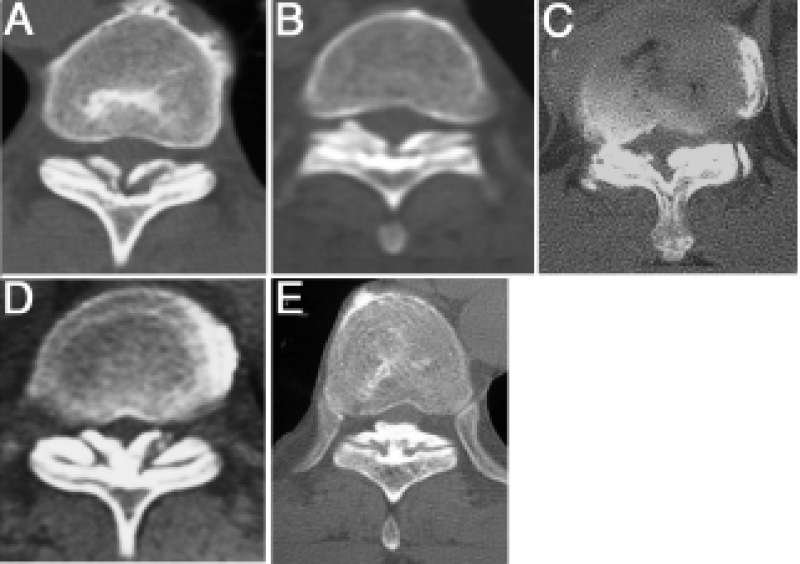

1. CT分型:按照轴位CT分为外侧型、延展型、肥厚型、融合型、结节型。

A. 外侧型(Lateral type):黄韧带囊部骨化,骨化物位于椎管外侧缘;

B. 延展型(Extended type):椎板间部黄韧带骨化;

C. 肥厚型(Enlarged type):黄韧带骨化侵及椎管内,但中线未融合;

D. 融合型(Fused type):双侧黄韧带骨化融合于椎管中线,但中线尚可见凹型切面;

E. 结节型(Tuberous type):双侧黄韧带骨化融合并形成骨化结节凸向椎管内。